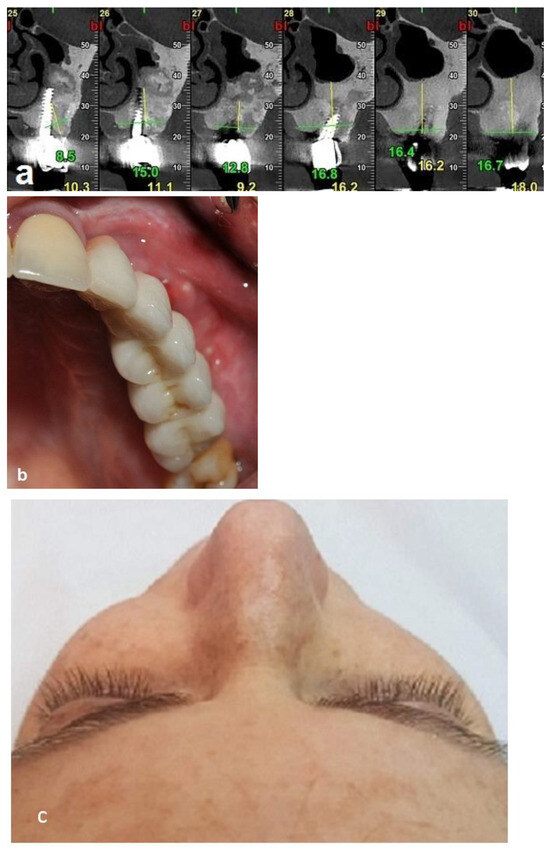

The second-stage surgical intervention was carried out 6 months later for dental implant placement. Four implants (SPI-Alpha Bio Tec., Modi'in-Maccabim-Re'ut, Israel), 3.75 diameter/13 mm length, were placed in the new bone site in the left posterior maxilla (Figure 6b). The dental implants were uncovered 4 months thereafter (Figure 7). An acrylic bridge was fitted over the implants as a temporary prosthesis (Figure 8), and this was replaced 12 months later by a fixed ceramic prosthesis (Figure 9a,b). The patient was then followed over 7 years.

First surgery: Healing at the 4 weeks follow-up visit after the surgery was uneventful (Figure 5a,b). During dental implant placement surgery that was carried out six months after the first surgery, a good bone quality was observed with normal bleeding (Figure 6a). All implants were clinically and radiographically successfully osseointegrated when exposed 4 months later (Figure 7). The final rehabilitation after one year, and throughout the long period of the follow-up, provides satisfactory esthetic and functional outcomes (Figure 10a,b). There were no obvious changes in the lesion dimensions after 7 years (Figure 10c).

Figure 6. Re-entry after 6 months and insertion of implants. (a) New bone volume with obvious bleeding was demonstrated. (b) Placement of four implants in the new bone.